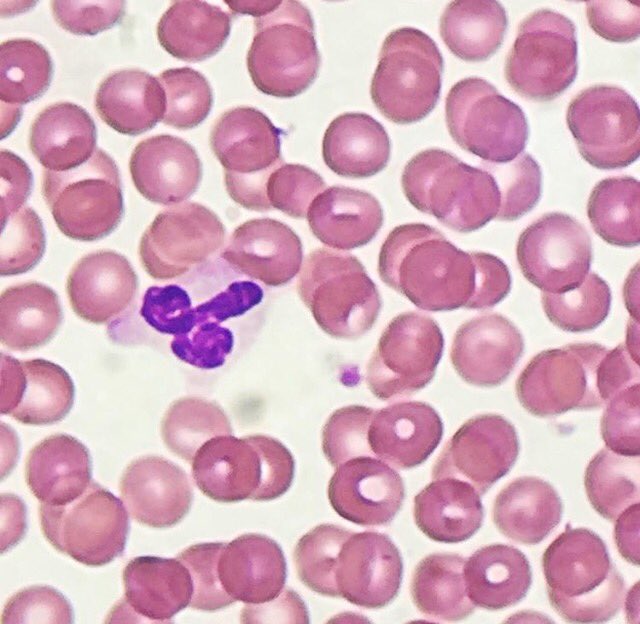

MARIBEL DONASTORG VITTINI Pembe Oltulu, MD The dx is T-cell lymphoblastic lymphoma. Not all starry sky pattern is Burkitt.

@bansar_bansaria Woo Cheal Cho, MD Bin Xu Sanjay Mukhopadhyay Jerad Gardner, MD Kalyani Bambal Xiaoyin "Sara" Jiang, MD (She/Her) @DrFNA Vijay Shankar S Bunina bodies in motor neurons of the anterior horn in ALS